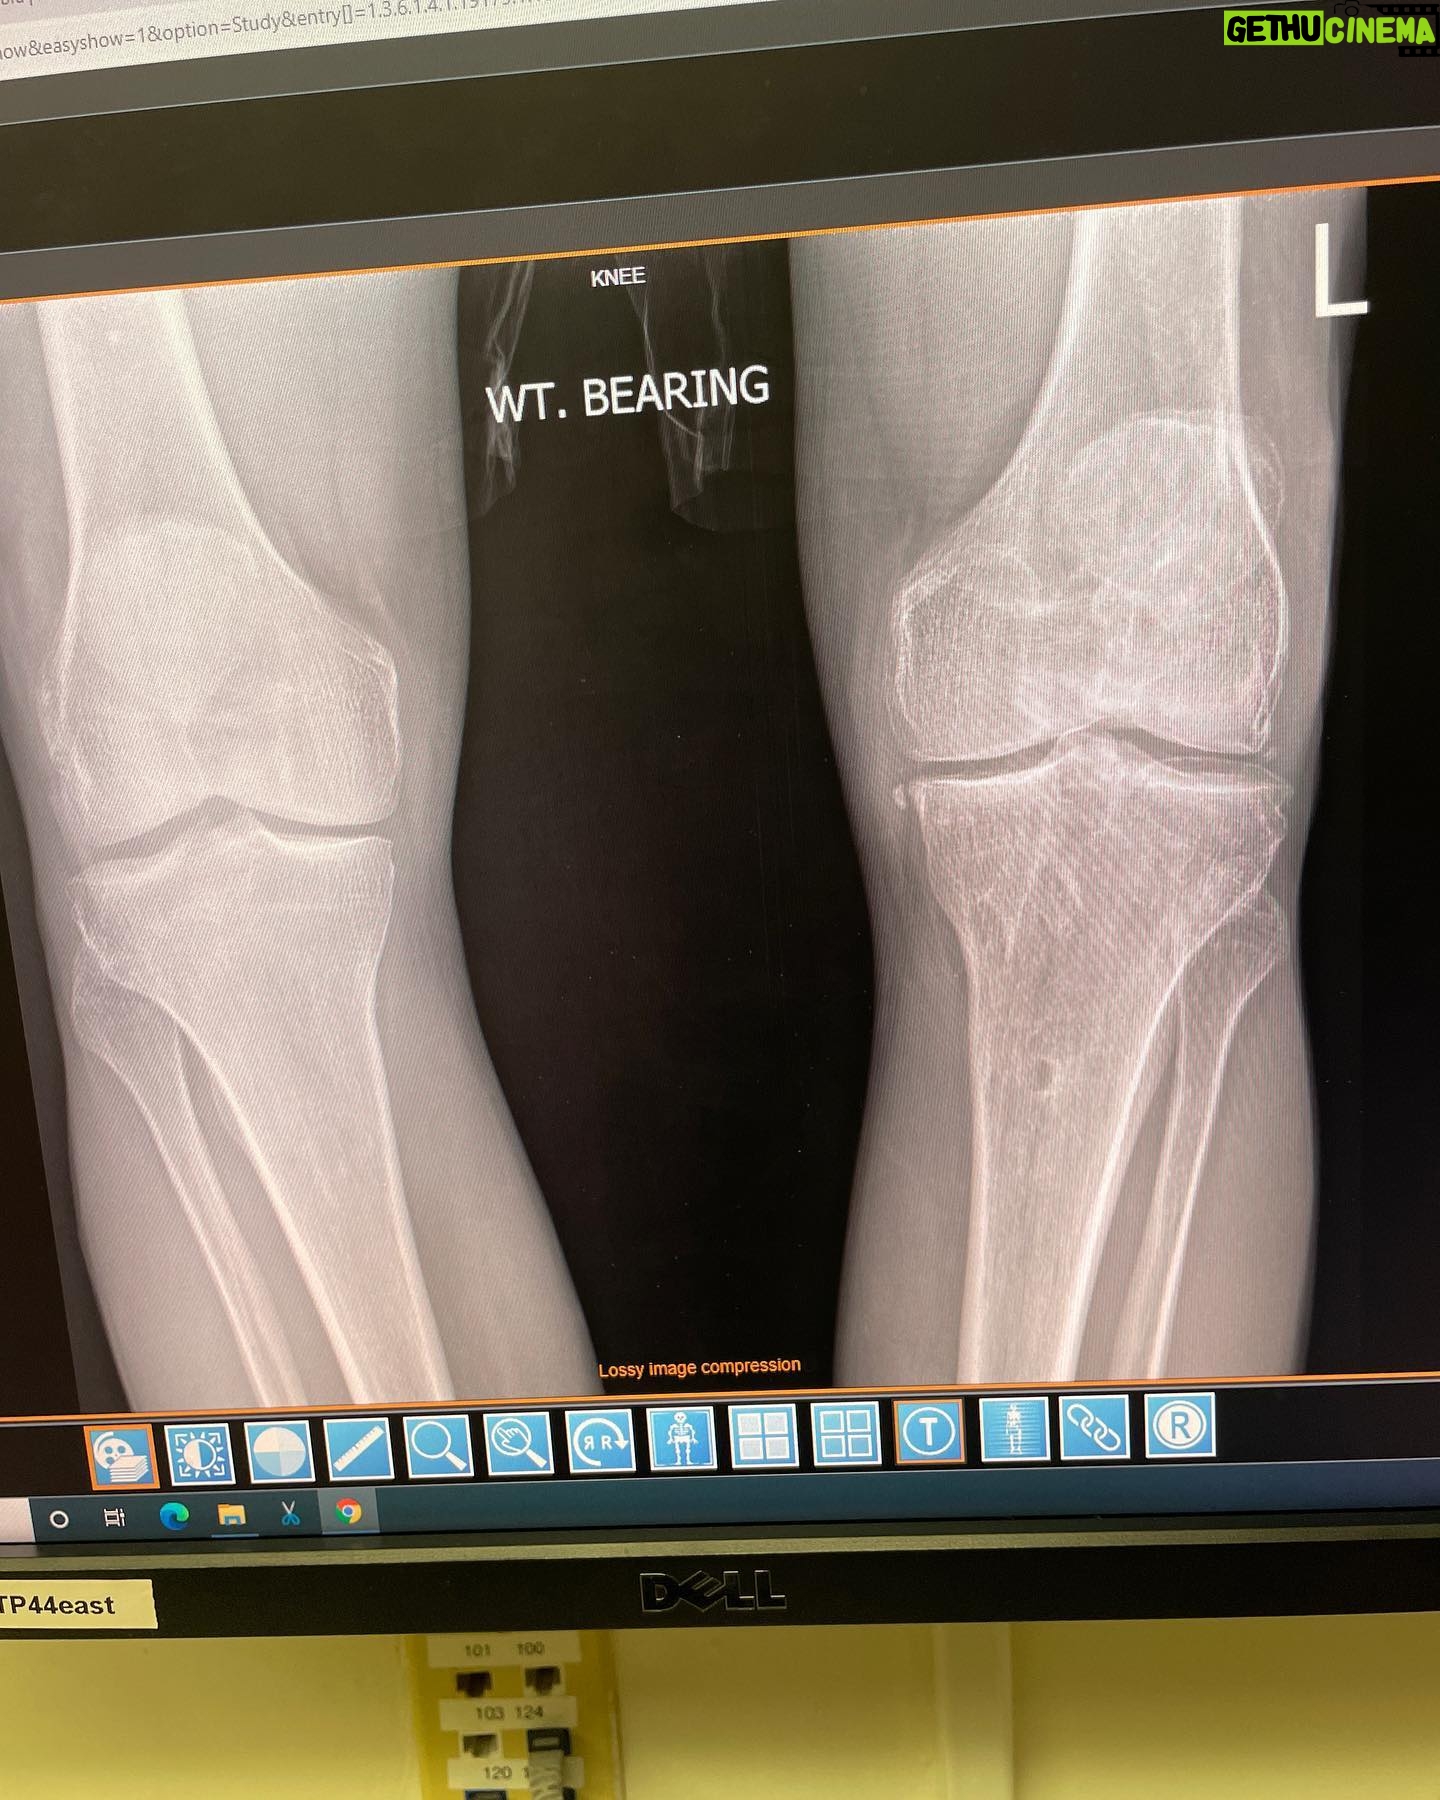

Caption : Seeing is believing, I’m always searching for the latest innovations with orthopedic medical science and was connected with @bioxcellerator_ through a good friend of mine @wolfmate about 2 years ago. I have had countless joint injuries and surgeries over the last 40 years and have some significant degeneration in several joints but the weight bearing joints are the most chronically painful. I have had 4 knee reconstructions on my left knee and about to have the 5th. Both of my knees have cartilage degeneration / arthritic changes from years of heavy abuse. BioXcellerator treated both knees along with every other joint in my body 14 months ago. Just prior to these treatments I had MRI scans and X-rays on every joint in my body. Here is proof of what the mesenchymal stem cells can do for degenerative joints. The first of these 2 films was shot 14 months by @dr.fabilus just prior to my treatment late June 2021 and the second film was shot 2 days ago September 9th 2022 by @dr.fabilus . The joint spacing has increased between my tibial plateau and my femoral condyle, which shows some level of cartilage regeneration in this 14 month time period and it will continue to improve for the next year or so! When I built this relationship with @bioxcellerator_ I told them I wanted to document the process and the results of my treatments and be completely transparent about the findings and they were so confident in the outcome they were happy for me to share the results. I’m so amazed by these results and very excited to be working with the most advanced scientists, doctors and business in the stem cell movement. Thank you so much @bioxcellerator_ @ericstoffers.ceo @dr.karolynnhalpert @dr_alejo @anahoyosf @dianis747 @drwilliamprevite @dr.fabilus @anirpo90 @joeygranathLikes : 6111

6.1K Likes – Danny Way Instagram